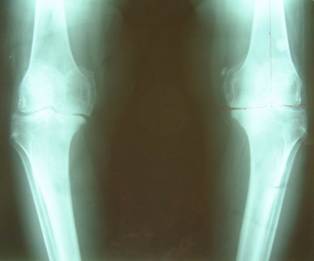

图 膝关节内翻的X线片,膝关节软骨碎裂、磨损,双膝内翻,关节间隙消失。